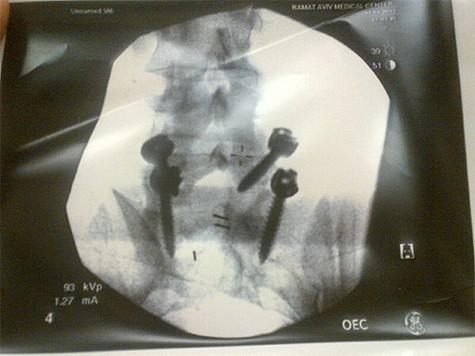

Рентген Евгения Плющенко. Фото: Twitter.com.

«Вот с чем теперь придется жить! В правом углу название клиники», - Рудковская.

Напомним, что накануне в одной из израильских клиник Плющенко была сделана на позвоночнике, из-за боли в фигурист был вынужден сняться с Чемпионата Европы в Загребе.